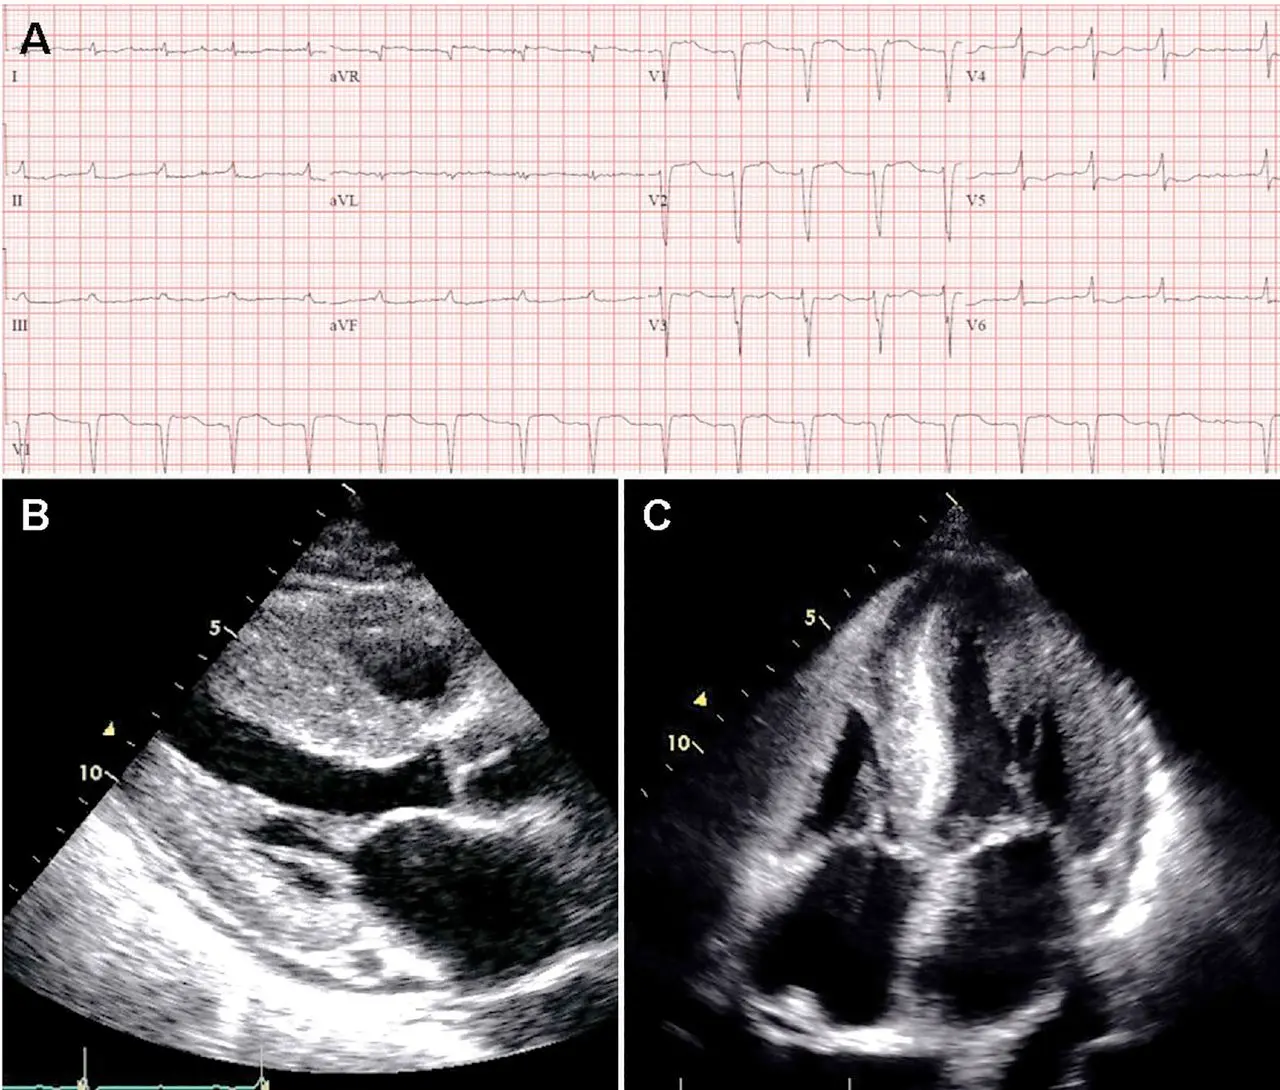

Discordance: LVH on Echo and Low-voltage on ECG

If you see LVH on echo but low-voltage on ECG, you should definitely suspect cardiac amyloidosis.

- ECG may show low-voltage and pseudo-infarct pattern (Q waves in early precordial leads, V1-V2) mimicking prior anteroseptal MI. 1

- 📝 only about 50% of patients with AL-CA and about 30% of patients with ATTR-CA meet true low-voltage criteria (QRS amplitude <5 mm in limb leads or <10 mm in precordial leads)

- Wide QRS complexes are more frequent in ATTR-CA and lower limb voltages are more frequent in AL-CA

Echo:

- LV wall thickness >1.2 cm (0.6 cm to 1.0 cm is normal) in the absence of hypertension should prompt suspicion for CA. 1

- LVH is most commonly symmetric, but you may see asymmetric septal hypertrophy, particularly in ATTRwt-CA 1

- Strain Imaging with “apical sparing,” in which the apical LV segments have normal or near-normal strain compared with the mid and basal segments. 1